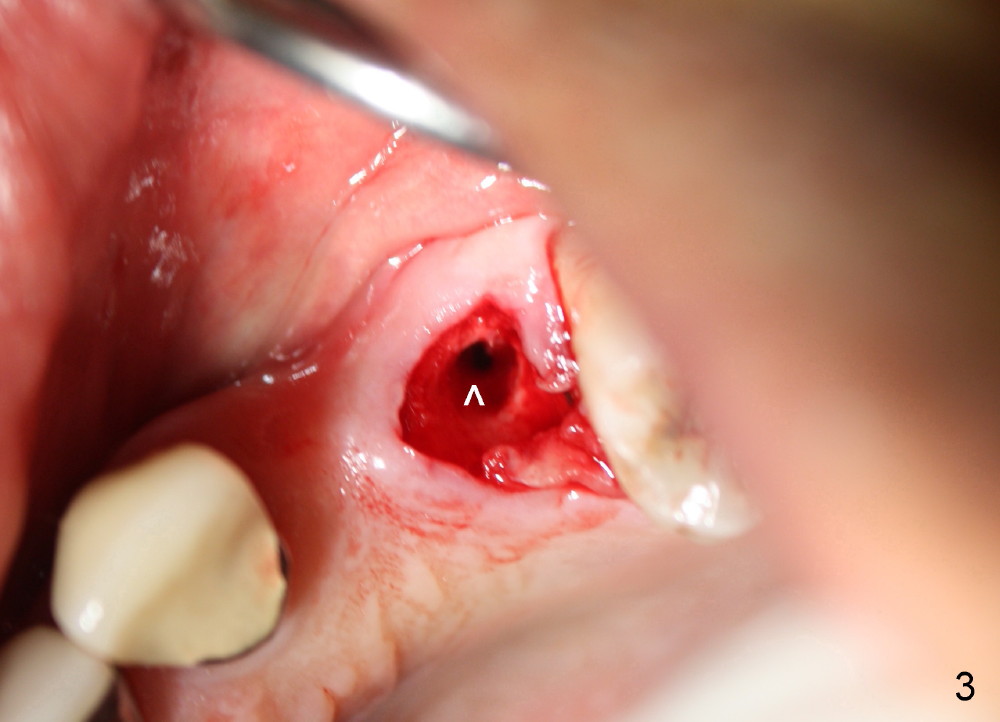

The anterior retainer is kept as a crown at #11 (Fig.2: C), whereas the residual root at the site of #13 is extracted with apical perforation (Fig.3 ^).  It is confirmed by Fig.4 (<).  To close the perforation, an osteotomy is initiated on the palatal wall of the socket with a 2 mm osteotome (Fig.5 insert: circle).  As the osteotomy is being enlarged by a 3 mm osteotome, the bone between the original socket and the osteotomy is being pushed buccally.  The former is being closed (Fig.5).  The osteotomy is finished with combination of osteotomes and reamers.  Fig.6 shows that a 5x14 mm tap is inserted at the site of #13 and that the sinus floor is lifted.  In fact the sinus membrane is partially torn at the osteotomy, which is repaired by insertion of Colla-form Dressing (Impladent), followed by autogenous bone (harvested from reamers) mixed with Osteogen  (Impladent).  A 5x14 mm implant is placed at the site of #13 with insertion torque more than 60 Ncm (Fig.7: I).  An incision is made at the site of #12 to start osteotomy with insertion of a parallel pin (Fig.7 P).  A 3 mm reamer is kept in place for position confirmation (Fig.8 R).  Due to ridge atrophy (Fig.2 arrowheads), a much smaller, but longer implant is placed at the site of #12 (Fig.9: 4x17 mm).  The autogenous bone harvested from #12 osteotomy is placed in the buccal gap of #13, followed by insertion of Colla-form Dressing (Fig.10 M).  To protect the membrane, a short abutment (4x3 mm) is temporarily placed (Fig.9,10 A) and perio dressing (Fig.9 D) is applied around the abutment and the interproximal areas of the neighboring teeth.  Usually perio dressing dislodges around 1 week postop, particularly for a large edentulous space.  In this case, the dressing is quite stable 11 days postop: the abutment (Fig.11 A) appears to contribute to retention of the dressing (D).